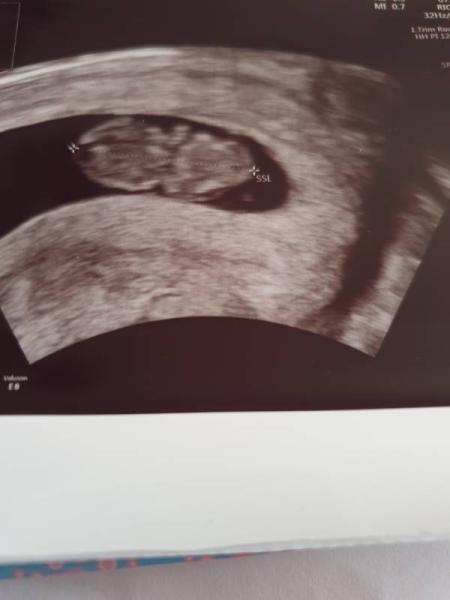

Also der Termin war super, mein Bärchen zappelt und das Herzchen blubbert, ich hab ein Video gemacht für meinen Mann das er unseren Krümel sehen kann. Allerdings wurde ich 1 Woche zurück datiert,obwohl mein Es definitiv am 29.07 war. Laut us bin ich 8+4... Wovon geh ich denn nun aus? 9 te Woche oder 10 te? Weil eigl wäre ich 9+5 So Bildchen häng ich an. In 4 Wochen darf ich wieder

Bild zu So zurück  vom Gyn - Forum für April - Mamis

Laut Kopf bis Fus 2,06 cm. Also würde 8+hinkommen